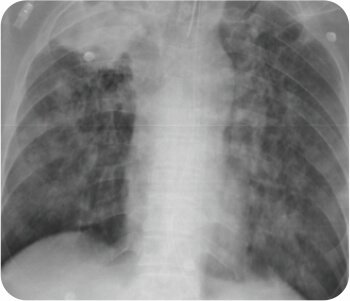

প্রাক প্রক্রিয়া এক্স-রে